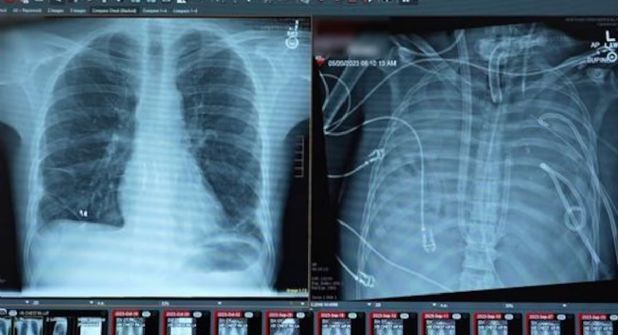

Un hombre de 33 años logró sobrevivir 48 horas sin pulmones gracias a un “pulmón artificial” desarrollado en el hospital Northwestern Medicine. El paciente permaneció conectado al sistema hasta recibir un trasplante doble de pulmón, un procedimiento pionero publicado en la revista científica Med.

Ante la gravedad del caso, el equipo médico decidió extirpar ambos pulmones y conectar al paciente a un sistema de "pulmón artificial" diseñado por el hospital.

Permaneció 48 horas sin pulmones, con el tórax vacío, conectado únicamente al pulmón artificial bajo monitoreo constante, hasta recibir el trasplante doble de pulmón.